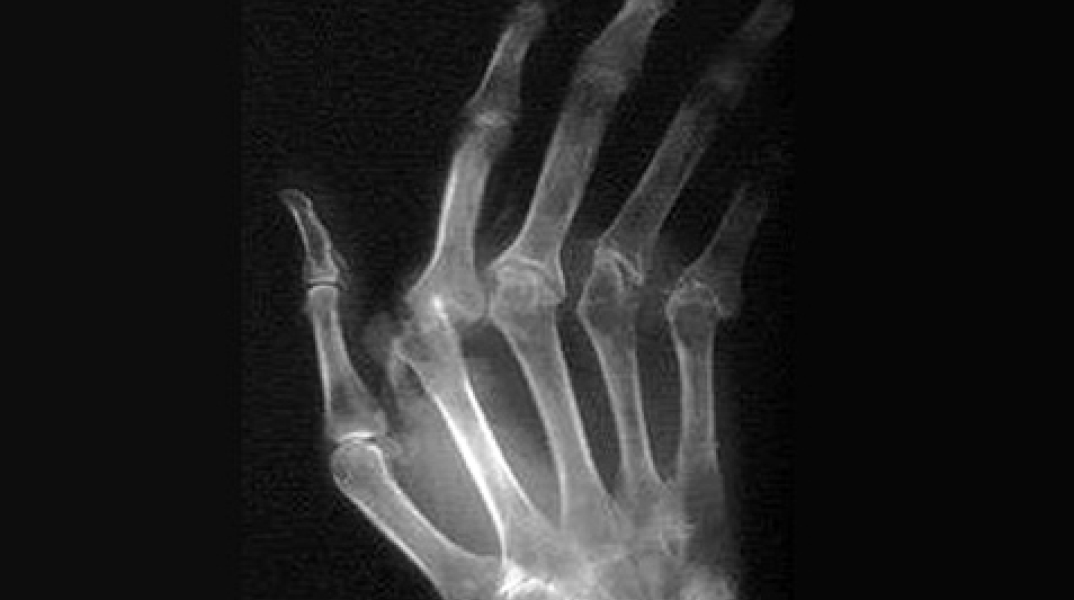

Νέα στοιχεία για τη ρευματοειδή αρθρίτιδα

Ομάδα επιστημόνων πιστεύει ότι η λύση βρίσκεται στα γονίδια

Διεθνής ομάδα επιστημόνων με επικεφαλής τον καθηγητή του Πανεπιστημίου Χάρβαρντ Ρόμπερτ Πλεντζ ανακάλυψε πάνω από 40 καινούριες περιοχές στο γενετικό υλικό (DNA), οι οποίες σχετίζονται με την πιθανότητα εμφάνισης της ρευματοειδούς αρθρίτιδας. Έως και 30.000 ασθενείς συμμετείχαν στην έρευνα, η οποία είναι η μεγαλύτερη μελέτη πάνω στη Γενετική που έχει γίνει μέχρι σήμερα. Οι επιστήμονες συνέκριναν το DNA ασθενών με ρευματοειδή αρθρίτιδα, με αυτό υγιών ατόμων και διαπίστωσαν ότι υπάρχουν 42 «ελαττωματικές» περιοχές που σχετίζονται με την ασθένεια. Η ομάδα ευελπιστεί τώρα ότι με τη χρήση των νέων ευρημάτων θα μπορέσει να παρασκευάσει νέα φάρμακα που θα μπορούν να αντιμετωπίζουν καλύτερα την ασθένεια ή ακόμα και να τη θεραπεύουν. Ο καθηγητής του Χάρβαρντ δήλωσε ότι η μελέτη προσφέρει μελλοντικά τη δυνατότητα να χρησιμοποιηθεί η Γενετική στην ανακάλυψη πρωτοποριακών φαρμάκων για την αντιμετώπιση πολύπλοκων ασθενειών.